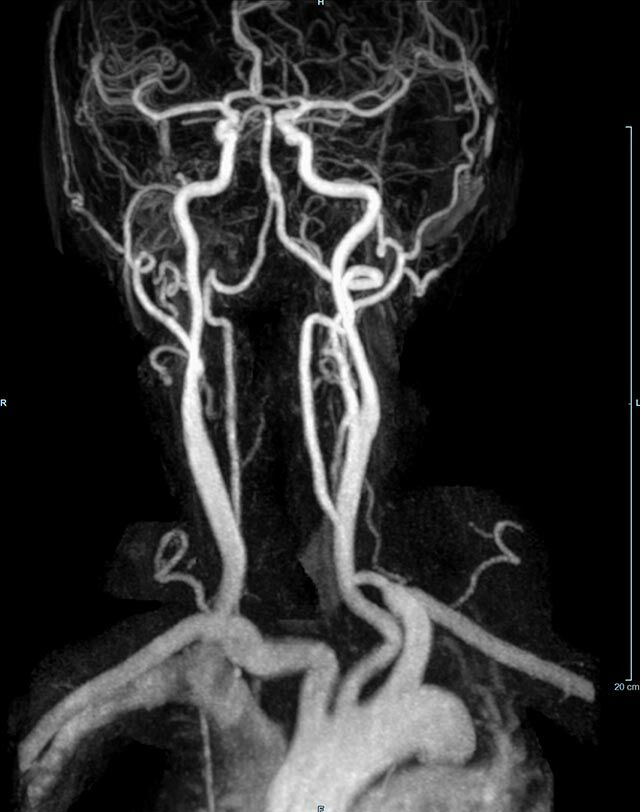

- MR-Angiografie ohne Kontrastmittel

- Time of Flight (TOF)-Angiographie

Je nach Fragestellung und Körperregion Gefäßdarstellung ohne Kontrastmittel bei Kontrastmittelunverträglichkeit oder terminaler Niereninsuffizienz möglich.

- MR-Angiographie mit Kontrastmittel

- Erfassung arterieller und venöser Gefäße/Bypässe aller Körperregionen mit 3D-Rekonstruktion